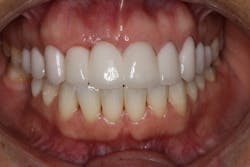

Reduction in quantity and quality of bone can also compromise functional and esthetic outcomes of both implants and fixed bridge restorations (figures 3 and 3a).

• Site development to increase hard and soft tissue for pontic sites in fixed bridge prosthetics (figures 4–4e)